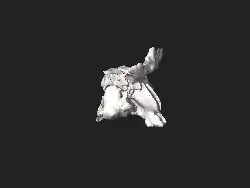

3D-Ansicht des Abgusses der Nasenhöhle und Nasennebenhöhlen eines Menschen